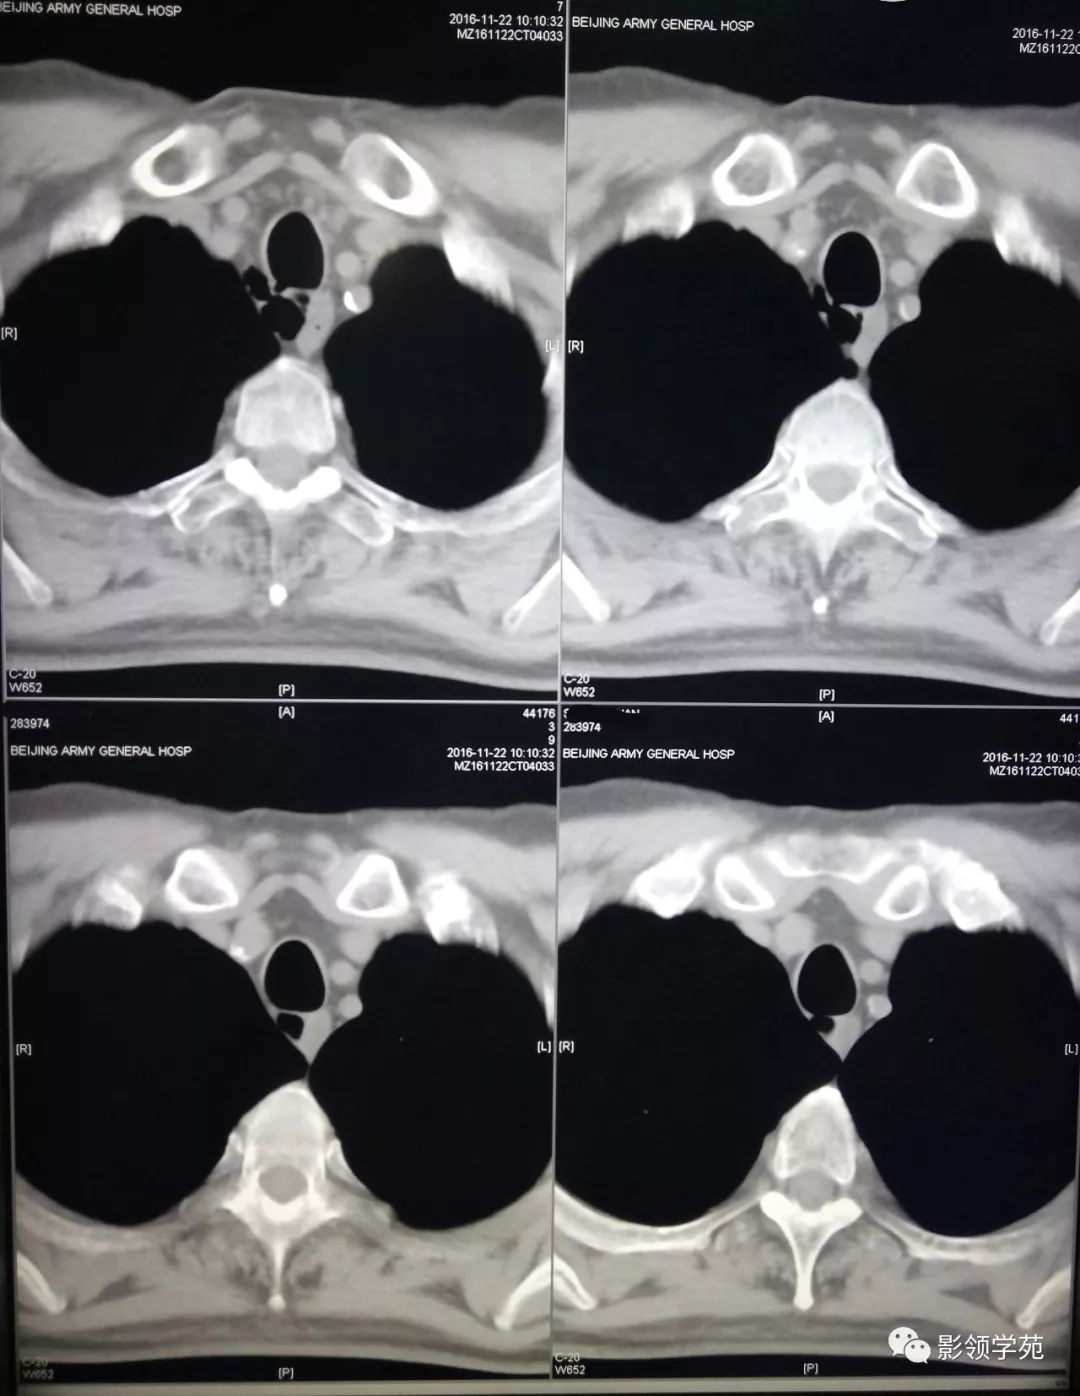

胸痛查体67气管憩室